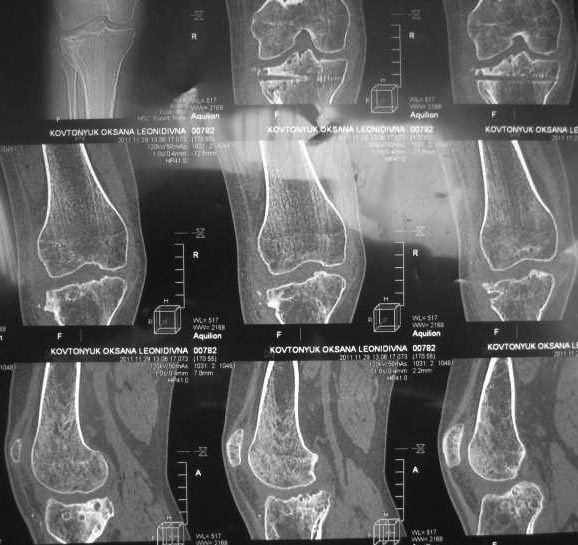

Жалобы на деформацию и нарушение функции правого коленного сустава .Внешний вид –вальгусная деформация на уровне коленного сустава .Коленный сустав стабильный, надколенник при сгибании в правильном положении.

Планируэм провести остеотомию на уровне проксимального метафиза большеберцовой кости .

Имя     : IMG_0041.jpg

Тип     : image/jpg

Размер  : 82942 байтов

Описание: отсутствует

Url     : http://weborto.net:8080/pipermail/ortho/attachments/20120513/91cb8573/attachment-0005.jpg